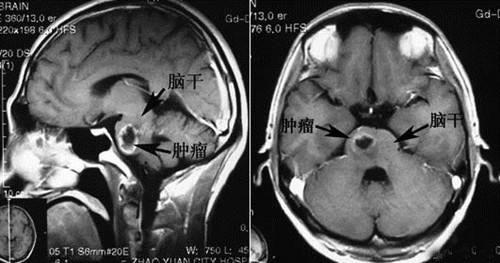

癌症最终死于什么原因?脑部肿瘤或者脑转移癌可出现脑水肿,脑疝,出现继发性癫痫,抽搐、昏迷,压迫呼吸中枢可引起死亡。其他癌症除非一些意外事件,比如肺癌突然的大咯血、突然的气道堵塞、胃癌消化道大出血、严重的梗阻或穿孔等。一般肿瘤晚期患者不会短期内或突然的死亡,都是一个缓慢过程,常见情况就是,患者进食越来越少、体力越来越弱、从能够自行活动到搀扶走到卧床不起、消瘦一日比一日明显,形成医学上所说的恶病质,虚弱到一定程度,患者会没有心跳呼吸迹象。所以,绝大多数癌症患者最终死于多器官功能衰竭。